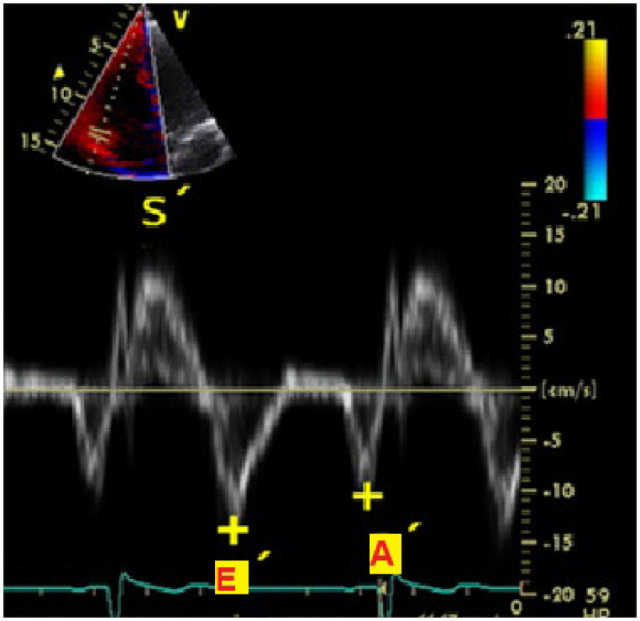

Methods: In this cross-sectional study, eighty CABG candidate adult patients were included. A history of previous heart surgery or arrhythmia were the main exclusion criteria. After recording demographic and clinical information, echocardiography of the right ventricle (RV) was performed the day before the surgery and seven days later. The functional parameters were obtained according to the Guidelines for the Echocardiographic Assessment of the Right Heart in Adults.

Results: Eighty patients with an average age of 60.25 ± 8.93 years participated in the study. Most patients were male (72.5%). Thirteen patients had RVDD before CABG (30.8% grade I and 69.2% grade II). All these 13 patients had RVDD grade II after surgery (P=0.046). Among 67 patients with normal RV function before CABG, RV function was normal in only 20 patients (29.9%) after CABG. The incidence of grade I and grade II post-CABG RVDD (post-coronary artery bypass grafting right ventricle diastolic dysfunction) was 11.9% and 58.2%, respectively (P<0.001). Univariate logistic regression analysis showed that there was no association between pre-CABG variables, neither demographic nor echocardiographic, and the occurrence of RVDD after CABG.